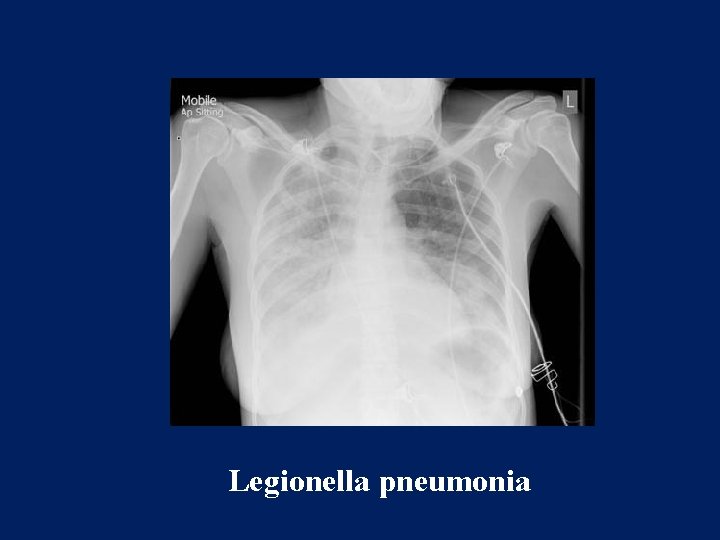

Radiology

Patchy reticular or reticulonodular opacities. Subsegmental and sometimes segmental atelectasis. Hilar adenopathy Pleural effusion

Legionella pneumonia